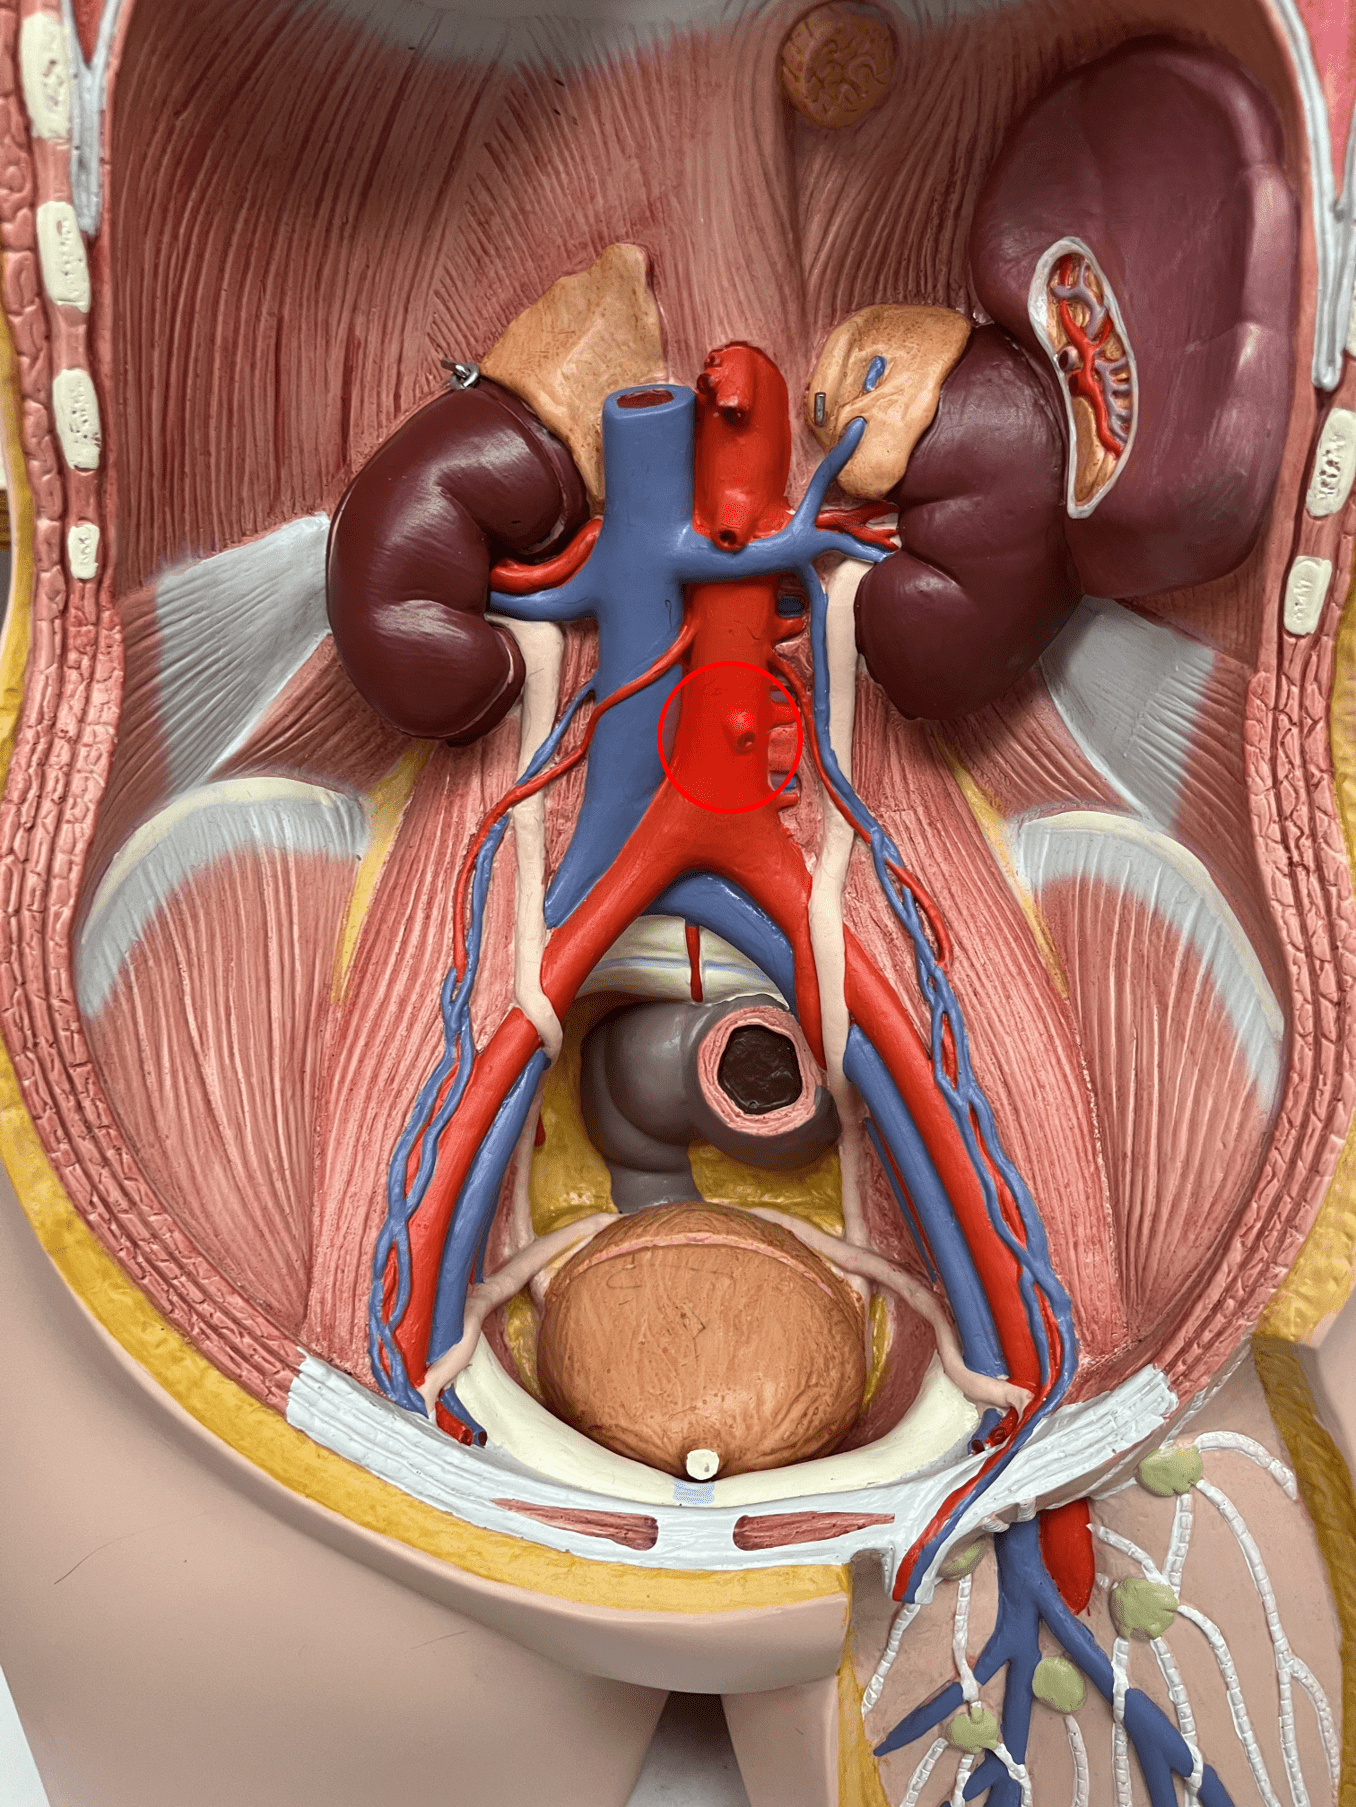

New cards

external elastic membrane